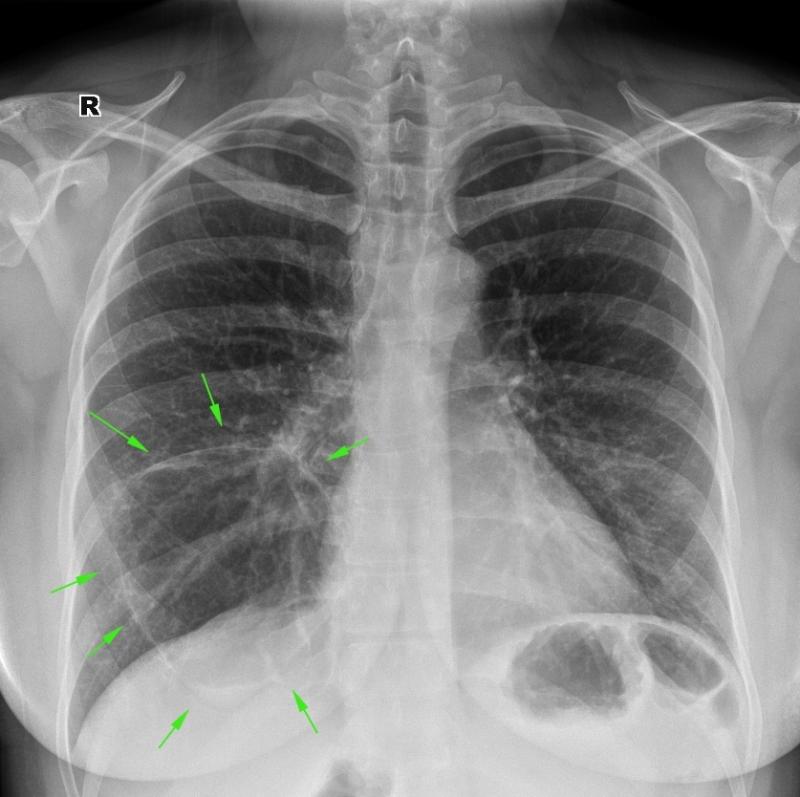

Симптомы и причины скопления воды в легких